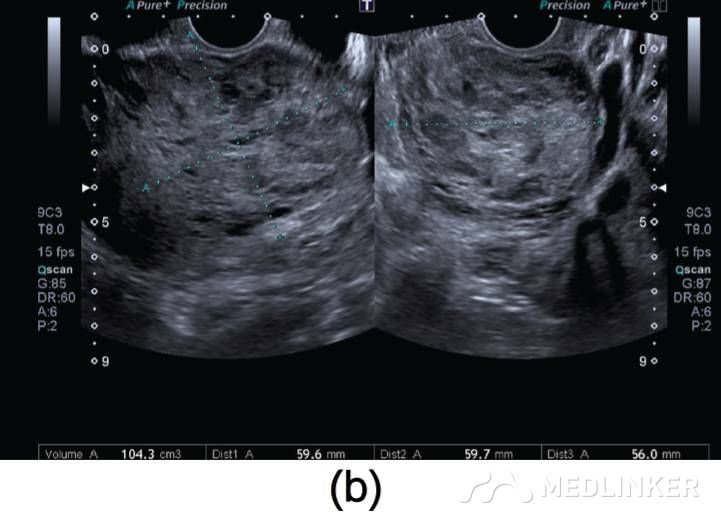

患者入院诊断:动静脉畸形。介入科会诊后行双侧子宫动脉栓塞术,栓塞材料为氰丙烯酸丁酯和碘油的混合物。该患者栓塞前后情况如图2所示。子宫动脉栓塞术后,患者未出现并发症,术后2天,患者出院,血hCG降至1766mIU/mL。术后1个月复查超声,未见血流,且受损范围缩小至61∗46∗52mm(77cm3)(图3),血hCG<0.5mIU/mL。  图2(a)右/左髂内子宫动脉造影术示:轻度扩张的子宫动脉显影浑浊,子宫内见多血管性肿块;(b)双侧子宫动脉栓塞术后图像   图3(a)2个月后的阴式超声示::受损范围缩小至61∗46∗52mm(77cm3);(b)多普勒彩超未见血流              根据年龄、生育要求、病变位置及范围大小选择不同的治疗方案,AVM主要的治疗方法是子宫切除和子宫动脉栓塞。育龄期有生育要求的子宫动静脉瘘患者首选治疗方法是子宫动脉栓塞,但是其远期的安全性尚存争议,而且行子宫动脉栓塞术后,妊娠的孕妇发生胎位异常、早产、产后出血及剖宫产的风险增大。        一些学者认为保守治疗适合无症状的AVM患者;还有学者认为出血少的AVM患者可以用甲基麦角新碱、促性腺激素释放激素类似物、达那唑等治疗。总之,目前对无症状的子宫动静脉瘘的治疗暂无统一的共识。        总之,子宫动静脉瘘是比较罕见且危险的临床疾病。通常,这种疾病常见于既往发生过自然流产的年轻女性,我们应该牢记行人工流产术(吸宮术)的患者,术后可能会继发子宫动静脉瘘,同时应该注意该病与其他疾病的鉴别。